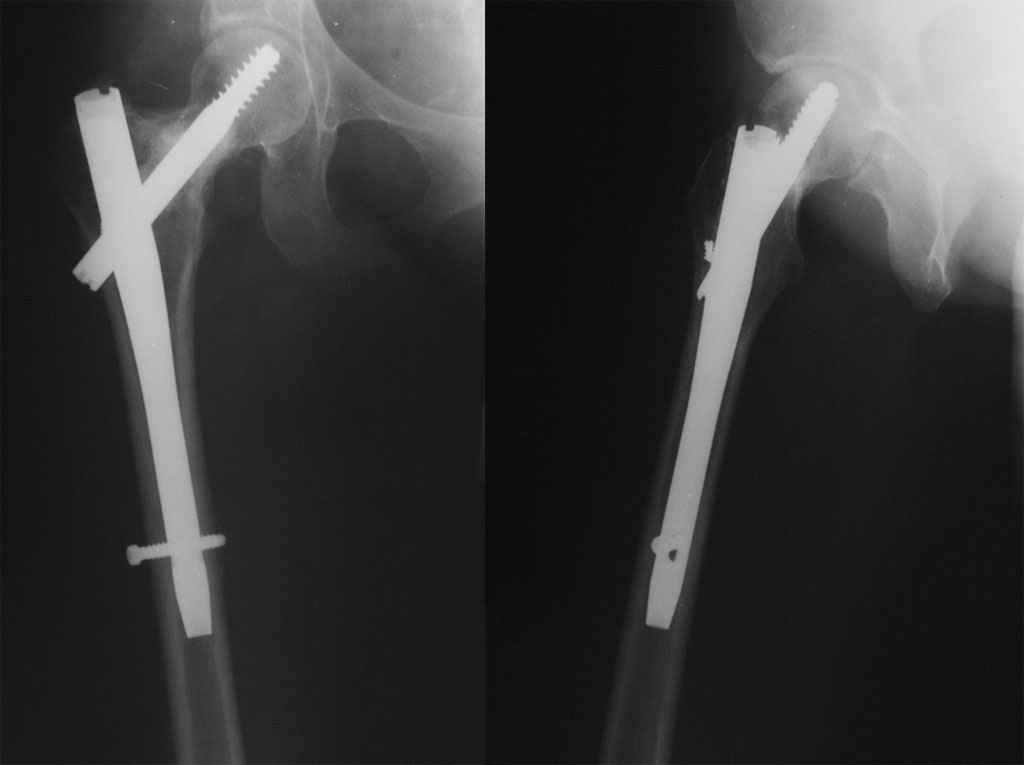

Продолжение http://www.weborto.net/forum/1216672567/ Контрольные рентгенограммы пациентки, которая в настоящий момент передвигается с полной нагрузкой на больную ногу. Жалоб не предъявляет. Сохраняется аритмичная походка, что связано со сформировавшимся стереотипом. Роды прошли в положенные сроки, ребенок растет и развивается нормально.

Спасибо за представленный результат. Можно поздравить с успехом. Как минимум есть сращение, и головка сохраняет форму.

Конечно, пациентку надо наблюдать и далее. Не уверен, что "аритмичную походку" (чтобы не сказать хромоту) надо связывать только с закрепившейся привычкой ходить. Все-таки и очаг в шейке был, и

кровоснабжение головки могло заметно снизиться. Надеюсь, у вас нет планов удалять гвоздь.